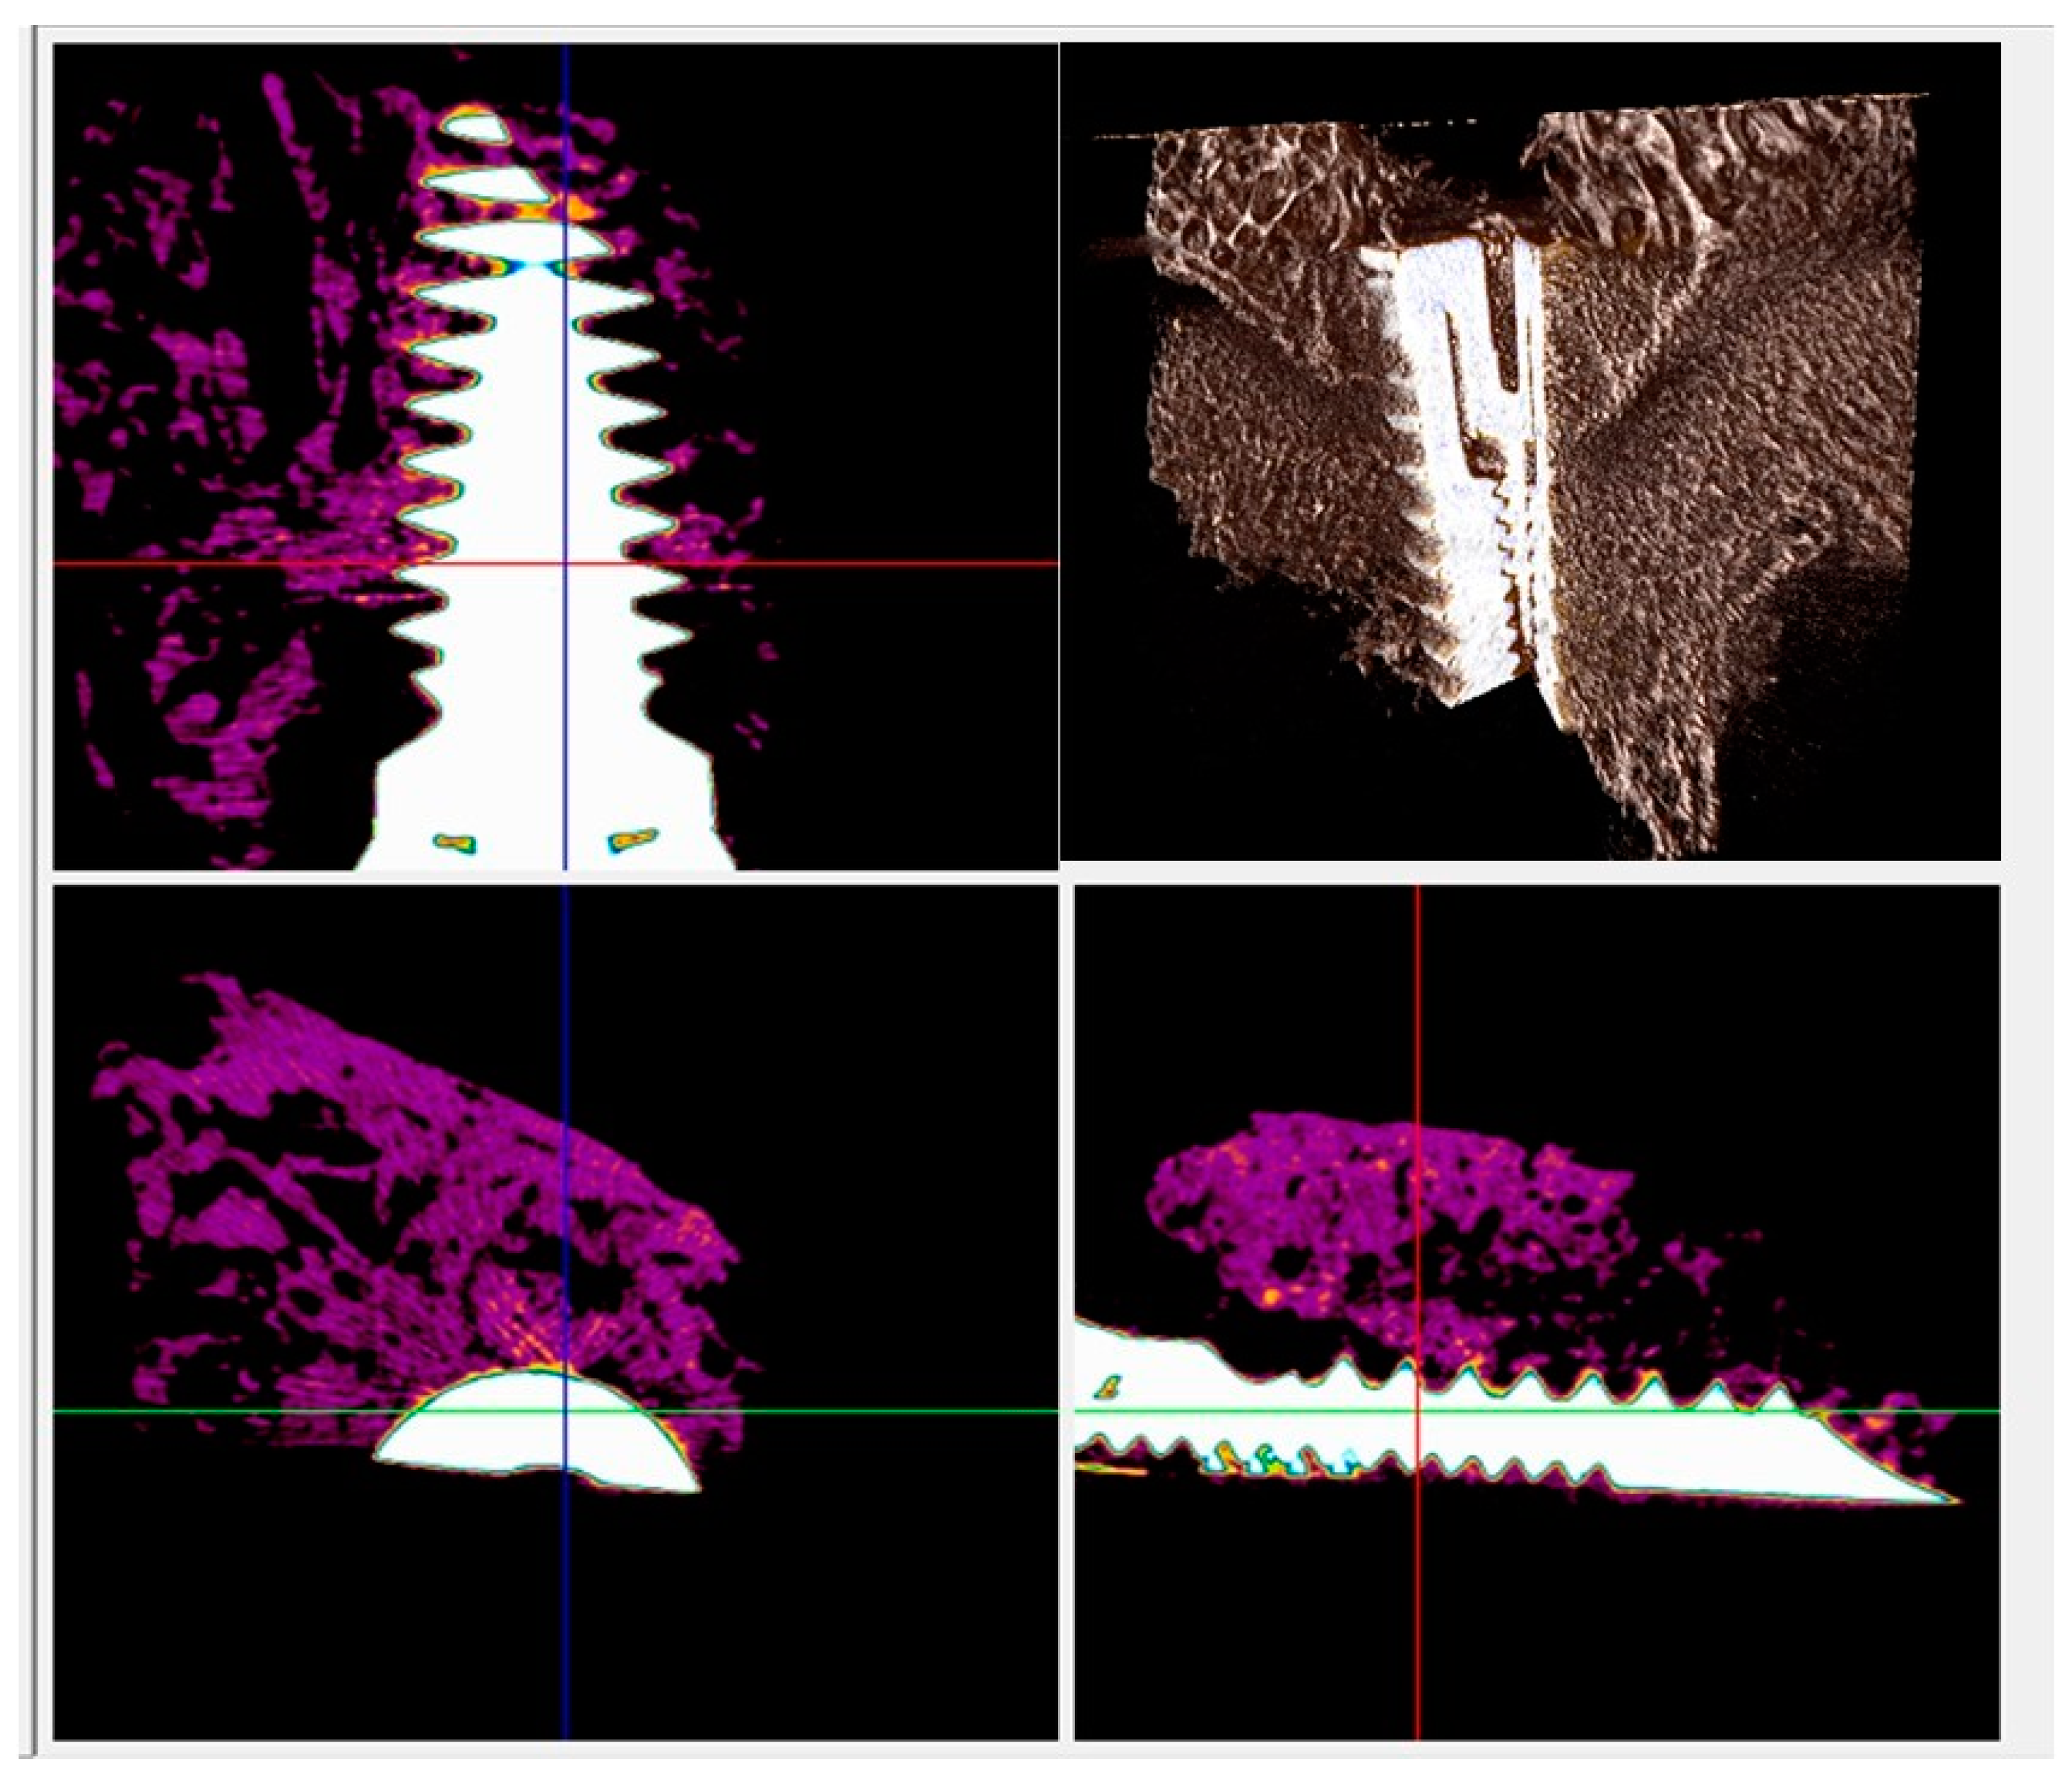

In both types of implants, a new bone in direct contact with the surface of the implant was visible in radiographs, and no gaps were detected at 15 days (Figure 5 and Figure 6). At 30 and 60 days the BD, BIC, and BAIT were more present in both implants. No bone resorption inflammation and/or osteolysis were present on either type of surface (Figure 6 and Figure 7).

Figure 6.

Micro-CT scans taken on the transection planes of the fixture. New bone formation around and in contact with the implant (purple or gray) was evident.

Figure 7.

Micro-CT scans for histomorphometric evaluation. The presence of newly formed bone around and in contact with the implant (purple or gray) was found.